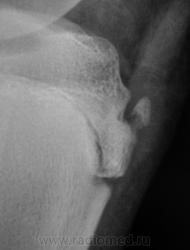

фрагментация бугристости Б\Б кости

Болезнь Осгут - Шлаттера, как-то не вдохновляет. Более склонен к консоидирующемуся отрывному перелому бугристости б/берцовой кости.

Более склонен к варианту окостенения, хотя травматический генез, как и асептический некроз (абсолютно согласен с Максималистом - при наличии клиники и анамнеза) с повестки дня окончательно, до выяснения оных, не снимаются.

Уважаемые коллеги! На мой взгляд, выявленное на рентгенограмме, образование костной плотности, с четкими, ровными контурами, однородное по своей структуре отношения с бугристости большеберцовой кости не имеет. Хотелось бы знать возраст пациента, его анамнез (спорт, травмы области коленного сустава). Больше похоже на обызвествления собственной связки надколенника. Дополнил бы УЗИ коленного сустава.

16 лет "учтенному лицу", ранее жалоб не было, рядом "мама", которой доктора посоветовали..., вот и вся история...